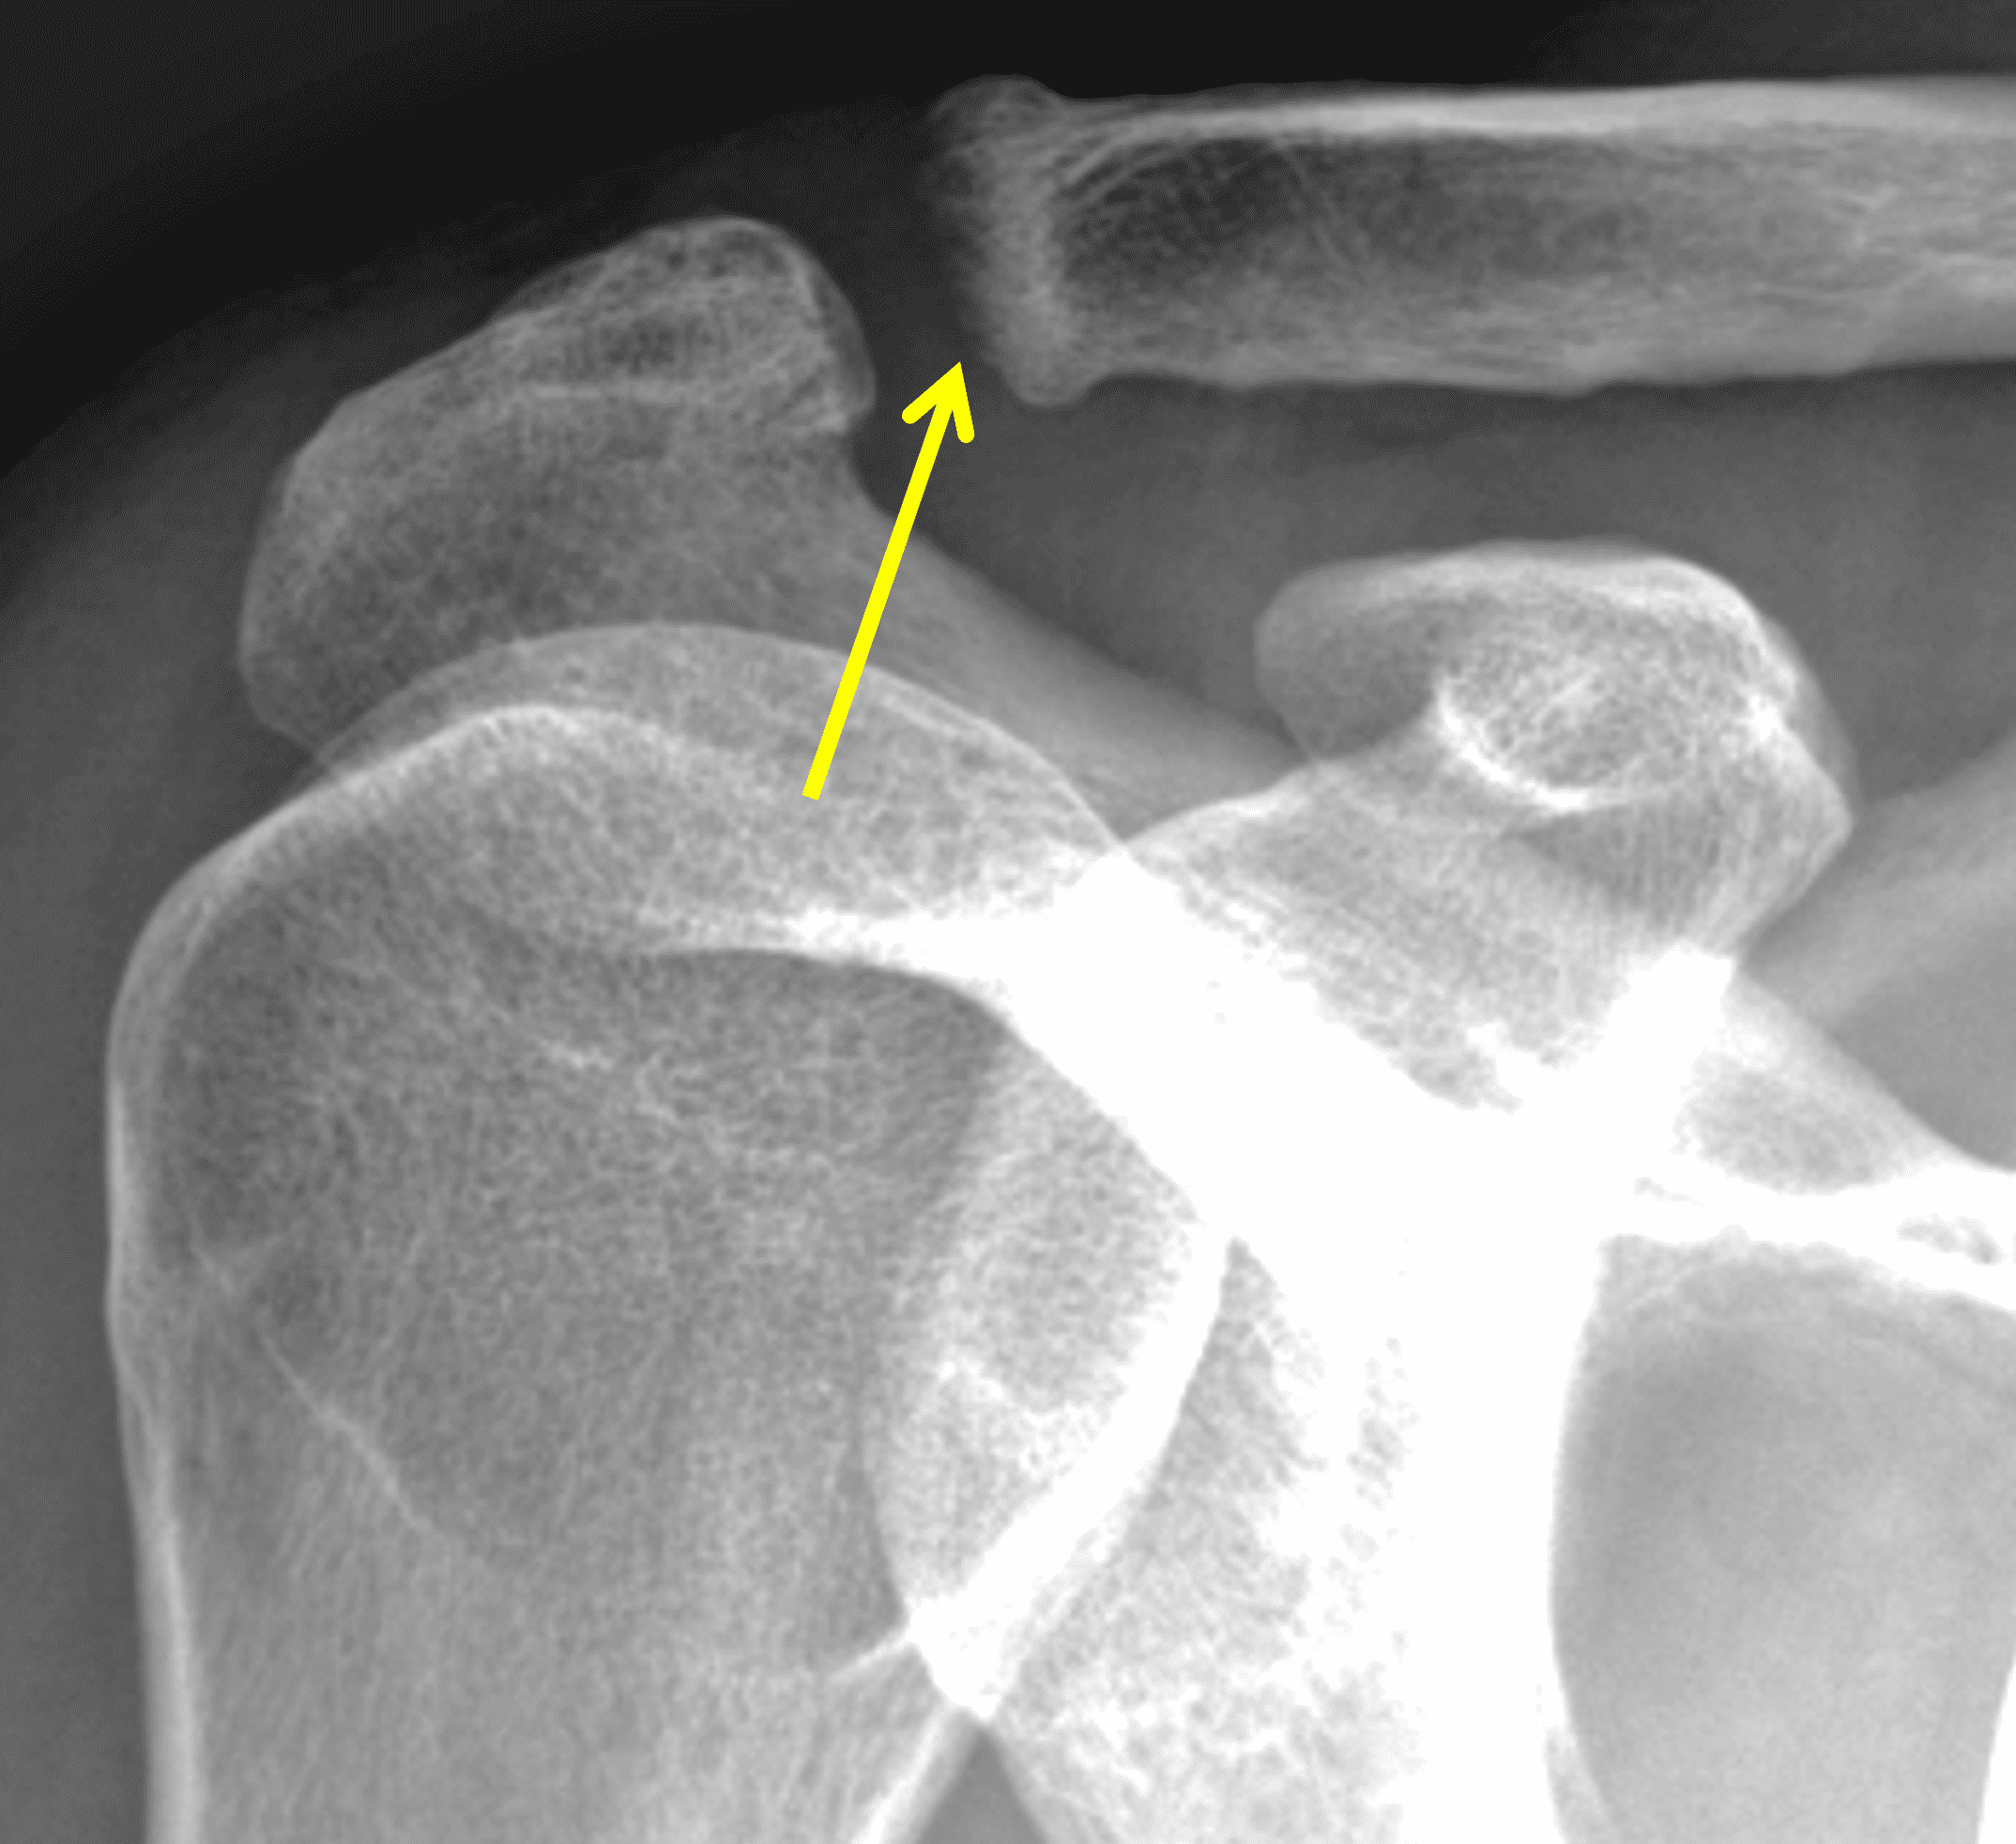

A 49-year-old male, avid weightlifter complains of chronic pain along the superior aspect of his right shoulder. He denies acute trauma. An AP radiograph (Figure 1A), as well as oblique coronal SPAIR (Figure 1B), axial fat-suppressed fluid sensitive (Figure 1C), and oblique sagittal T2-weighted images (Figure 1D) are shown. What are the findings? What is your diagnosis?

Radiographs: Initial radiographs may be normal or show features of other common unrelated AC joint pathology such as osteoarthritis. As inflammation and hyperemia in the distal clavicle progresses, bone density in the distal clavicle can decrease with indistinctness or discontinuity of the subchondral bone plate (Figure 3).  This so-called resorptive phase may also include frank erosions in the distal clavicle or a faint sclerotic line in the medullary space of the distal clavicle parallel to the bone end. Varying degrees of surrounding soft tissue swelling may be visible.  Later, during the late healing phase when symptoms have usually resolved, the distal clavicle may return to a normal radiographic appearance; a sclerotic line parallel to the distal bone end is visible after healing in some cases (Figure 4).  In patients with severe initial bone loss, re-cortication of the resorbed bone and erosions can occur leaving residual bone loss and contour defects in the distal clavicle. While it is typically not a primary modality for the diagnosis of DCO, CT demonstrates the same bone findings as radiographs.